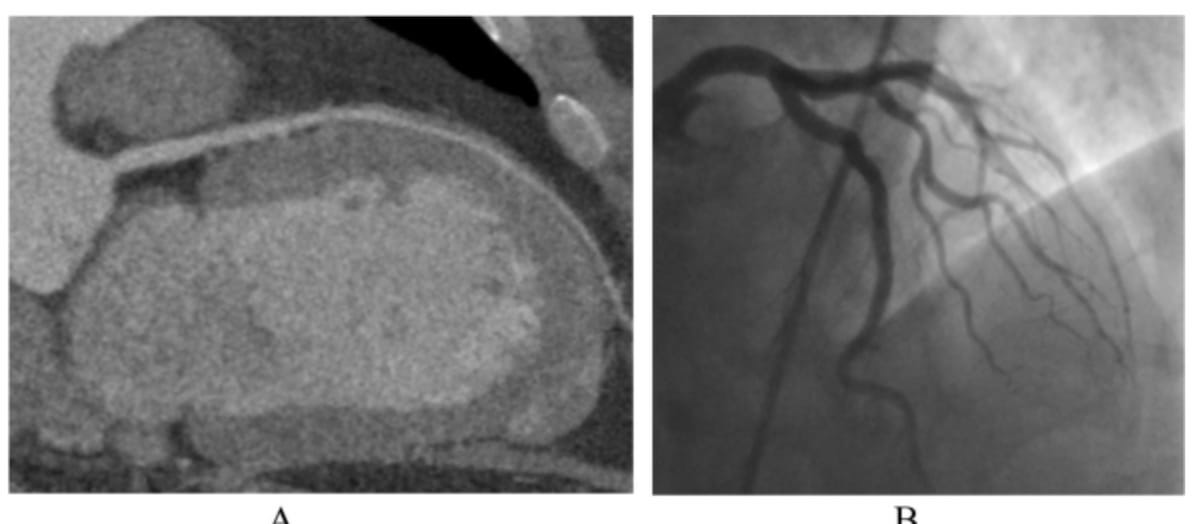

In a study cohort of patients undergoing pre-operative workup for transcatheter aortic valve replacement (TAVR), researchers found the use of photon-counting CT for ultra-high resolution coronary CT angiography had a 96 percent sensitivity rate and an 84 percent specificity rate for the detection of coronary artery disease (CAD).